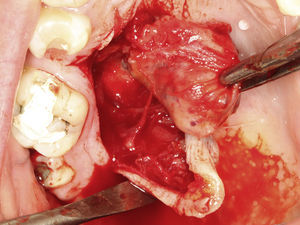

Casos clínicosCaso 1Paciente do sexo masculino, 68 anos de idade, leucoderma, procurou a Clínica de Estomatologia do Departamento de Odontologia da Pontifícia Universidade Católica de Minas Gerais (PUC Minas) queixando‐se de aumento de volume no palato, com tempo de evolução de 2 anos e discreta sintomatologia dolorosa. A anamnese não revelou alterações sistémicas. Ao exame clínico extraoral não foram observadas alterações. O exame clínico intraoral mostrou lesão nodular, pediculada, de consistência firme, localizada no palato duro do lado direito, entre os pré‐molares superiores e a rafe palatina, medindo aproximadamente 2cm na sua maior extensão. Foi realizada uma radiografia oclusal de maxila que não mostrou alterações ósseas. As hipóteses diagnósticas de neoplasia de glândula salivar e neoplasia mesenquimal benigna foram consideradas. Foi realizada biópsia incisional com diagnóstico anatomopatológico de adenoma pleomórfico. O tratamento proposto para a lesão foi a remoção cirúrgica conservadora. Paciente retornou após 4 semanas exibindo, ao exame intraoral, ulcerações na mucosa que recobria a lesão (fig. 1). Inicialmente, foi realizada anestesia local por meio da técnica supraperiosteal para bloqueio de ramos do nervo palatino maior, com cloridrato de lidocaína 2% e epinefrina 1:100.000 (ALPHACAINE 100®, DFL, Rio de Janeiro, Brasil). Em seguida, foi realizada incisão na base da lesão com bisturi lâmina 15 (Solidor, São Paulo, Brasil) e, após o descolamento do retalho mucoso palatino, a lesão foi exposta e removida (fig. 2). Foi realizada limpeza da ferida cirúrgica e sutura com fio seda Ethicon™ 4.0 (Johnson & Johnson, São Paulo, Brasil) (fig. 3). A lesão excisada (fig. 4) foi fixada em solução de formaldeído a 10% e enviada para exame anatomopatológico no Laboratório de Patologia Bucal da PUC Minas.

Paciente do sexo feminino, 31 anos de idade, leucoderma, foi encaminhada pelo cirurgião‐dentista à Clínica de Estomatologia do Departamento de Odontologia da PUC Minas para avaliação de lesão nodular no palato duro com diagnóstico histopatológico de adenoma pleomórfico, obtido por meio de biópsia incisional. Durante a anamnese, a paciente relatou a evolução da lesão há 4 anos com característica assintomática. Relatou estar no sexto mês de gestação e não apresentava outras alterações sistémicas. O exame extraoral mostrou ausência de alterações. Ao exame intraoral, observou‐se um aumento de volume bem delimitado no palato duro do lado direito, de consistência firme e coloração semelhante à da mucosa normal, medindo aproximadamente 2,5cm, exibindo pequena área de ulceração no local da realização da biópsia incisional (fig. 9). O exame radiográfico não mostrou alterações. O tratamento proposto foi a remoção cirúrgica conservadora e confecção de placa palatina em acrílico com grampos retentores para minimizar o desconforto pós‐operatório. Foi realizada anestesia local com lidocaína 2% e epinefrina 1:100.000 (ALPHACAINE 100®, DFL, Rio de Janeiro, Brasil), seguida de incisão semilunar com bisturi lâmina 15 (Solidor, São Paulo, Brasil) e rebatimento do retalho mucoso. Como a lesão se apresentava encapsulada, foi possível destacá‐la da mucosa suprajacente com facilidade (fig. 10). O retalho foi reposicionado por meio de pontos isolados (fig. 11) e a lesão (fig. 12) foi fixada em formaldeído a 10% para realização de exame anatomopatológico no Laboratório de Patologia Bucal da PUC Minas. Em seguida, foi colocada a placa de acrílico (fig. 13) para proteção da região operada e controlo da sintomatologia dolorosa.